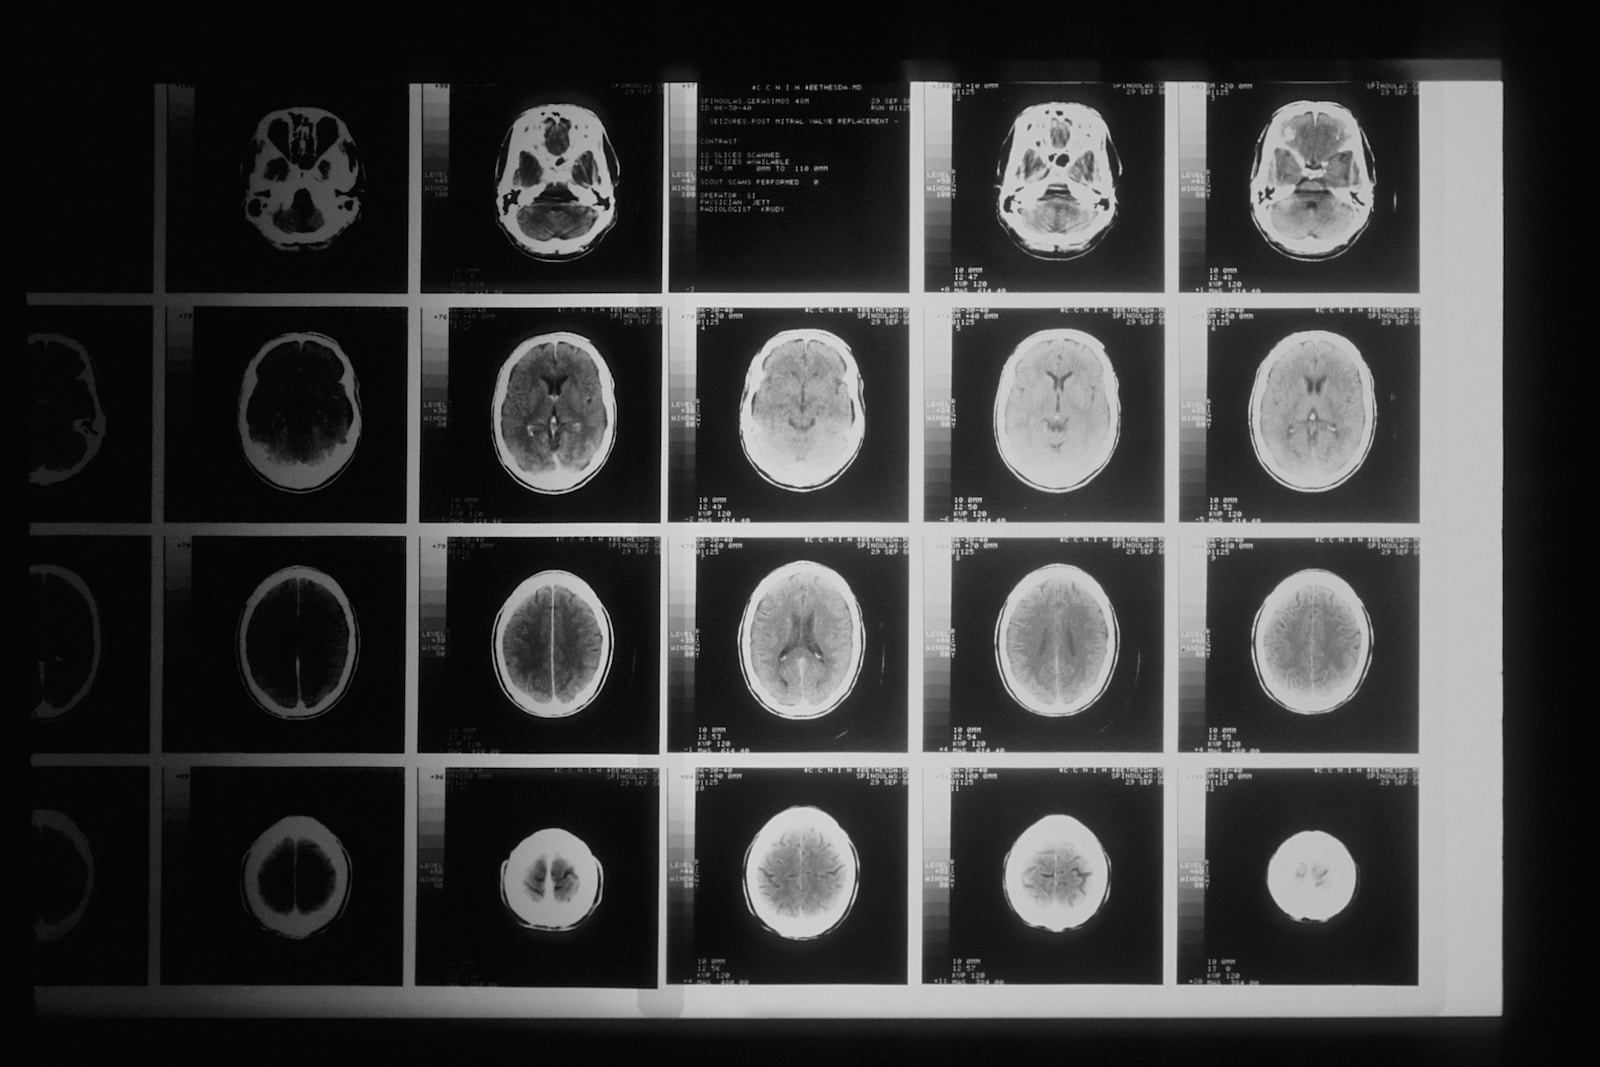

Mozog je veľmi zložitý, komplexný a jeden z najdôležitejších orgánov v ľudskom tele, preto akékoľvek jeho poškodenie, môže mať a aj máva hlboký dopad na zdravie jednotlivca. Poškodenie mozgu môže byť spôsobené celou radou rôznych patologických situácii, ako napríklad súčasť mnohých diagnóz, vrátane mŕtvice, traumatických poranení mozgu a nádorov mozgu.

Človek, ktorý stratil schopnosť cítiť smútok

Odkedy v roku 2004 utrpel mozgovú príhodu, Malcolm Myatt nebol schopný pociťovať smútok. Mŕtvica, ktorú utrpel, postihla predný lalok jeho mozgu, konkrétne oblasť, ktorá zodpovedá za reguláciu emócií. Ktovie, či je to výhoda alebo nie, ale Malcolm dokáže byť len neustále šťastný.

Nádor na mozgu zmenil človeka na pedofila

Jednalo sa o 40-ročného učiteľa, ktorý začal pozerať detskú pornografiu, navštevovať prostitútky a obťažovať deti. Až keď ho uznali vinným a začal pociťovať problémy s rovnováhou, ho vyšetrili a objavili nádor na mozgu.

Odstránili ho, ale o niekoľko rokov neskôr sa mu vrátil aj s nekalým nutkaním.